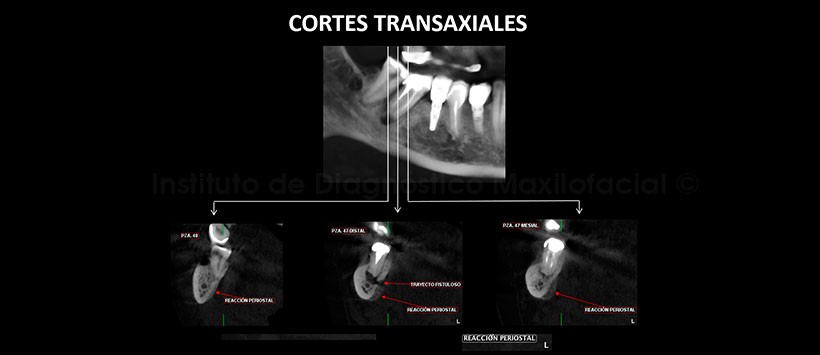

A la evaluación de la tomografía volumétrica (CBCT) mediante cortes axiales, coronales, sagitales (Figura 2) y transaxiales (Figura 3), se encontró una imagen hipodensa periapical de pieza 47 compatible con un proceso osteolítico que generaba un trayecto fistuloso hacia lingual, hiperdensidad ósea difusa circundante que compromete a las corticales del conducto dentario inferior a este nivel y como hallazgo se encontró la presencia de una reacción periostal dependiente de la tabla ósea lingual. Además se encontró como variante anatómica la bifurcación del conducto dentario inferior derecho.